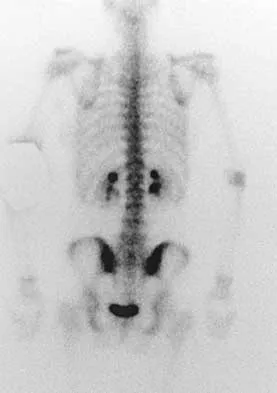

A 73-year-old man reports increasing back and lower extremity pain. A bone scan is shown in Figure 31. What is the most likely diagnosis?

Explanation

The bone scan reveals lesions throughout the skeleton. The patient's age, gender, and pain pattern are consistent with metastatic prostate cancer. Multiple myeloma typically does not have enough osteoblastic activity to produce this bone scan. The patient's age is not consistent with metastatic neuroblastoma (a pediatric disease). Polyostotic fibrous dysplasia may involve multiple active lesions in younger patients but does not have such a widespread distribution of lesions. Hodgkin's lymphoma can involve bone, but the widespread discrete appearance on this bone scan is most consistent with metastatic prostate cancer. In a patient with widespread bone metastases from prostate cancer, bisphosphonates may play a critical role in treatment by decreasing pain and the number of fractures. Roudier MP, Vesselle H, True LD, Higano CS, Ott SM, King SH, Vessella RL: Bone histology at autopsy and matched bone scintigraphy findings in patients with hormone refractory prostate cancer: The effect of bisphosphonate therapy on bone scintigraphy results. Clin Exp Metastasis 2003;20:171-180.